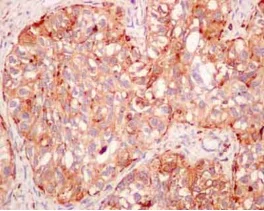

Immunohistochemistry (Formalin/PFA-fixed paraffin-embedded sections) - Anti-Cathepsin Z antibody [EPR14357] - BSA and Azide free (AB250229)

This data was developed using ab180580, the same antibody clone in a different buffer formulation.

Immunohistochemical analysis of paraffin-embedded Human ovarian carcinoma tissue labeling Cathepsin Z with ab180580 at 1/100 dilution followed by pre-diluted HRP-conjugated secondary antibody and counter-stained with Hematoxylin.

Perform heat mediated antigen retrieval with EDTA buffer pH 9 before commencing with IHC staining protocol.